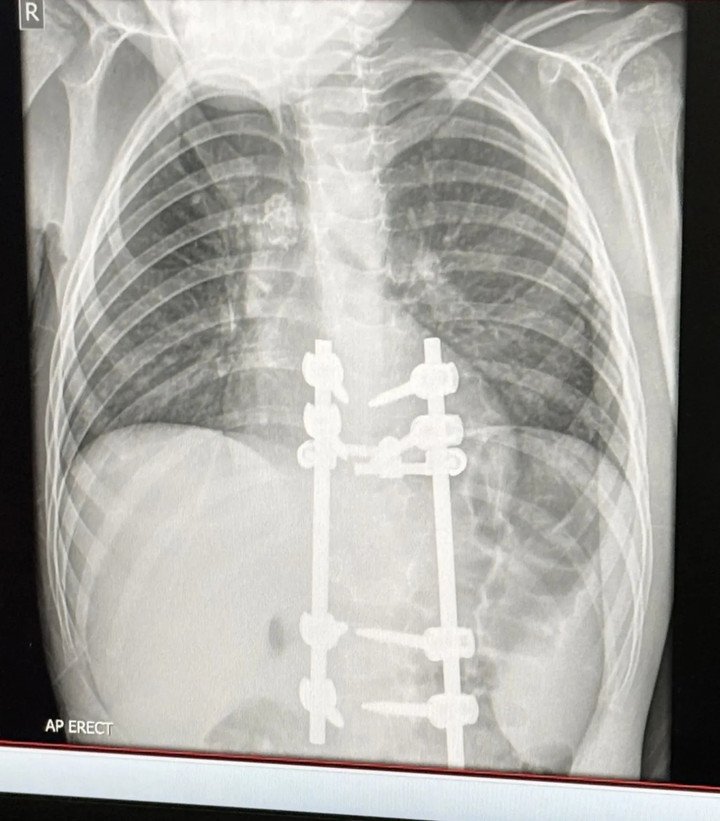

Tuy nhiên, mọi thứ chuyển biến xấu nhanh chóng từ tháng 6/2025, khi Elliot than phiền hai chân cậu bé không thể cử động. Megan lập tức đưa con tới phòng cấp cứu và được chỉ định khám chuyên sâu. Tại đây, kết quả X-quang cho thấy các hạch bạch huyết bị vôi hóa trong phổi, gợi ý tình trạng nhiễm khuẩn lâu dài trước đó.

Các xét nghiệm tiếp theo giúp xác định Elliot bị mắc lao cột sống (spinal tuberculosis) – dạng lao nguy hiểm ngoài phổi, trong đó vi khuẩn lao không chỉ ảnh hưởng hệ hô hấp, mà còn tấn công vào hệ xương, gây các triệu chứng về thần kinh và vận động.

Sau khi đánh giá kỹ lưỡng, các bác sĩ chỉ định phẫu thuật đối với cậu bé Elliot, nhằm giải phóng chèn ép ống thần kinh và ổn định lại cấu trúc cột sống.

Ca phẫu thuật đầu tiên đã thành công, Elliot hiện có thể đi bộ, nhưng chưa được phép chạy nhảy. Cậu bé sẽ đối mặt với lần phẫu thuật thứ hai trong vòng sáu tháng tới, nếu dấu hiệu tổn thương lao trên cột sống không thu nhỏ. Theo chia sẻ từ người mẹ, dáng đi của Elliot đã trở lại bình thường, các cơn đau dữ dội ở vùng lưng cũng biến mất.

Kết quả X-quang của Elliot sau phẫu thuật. (Ảnh: Kennedy News)